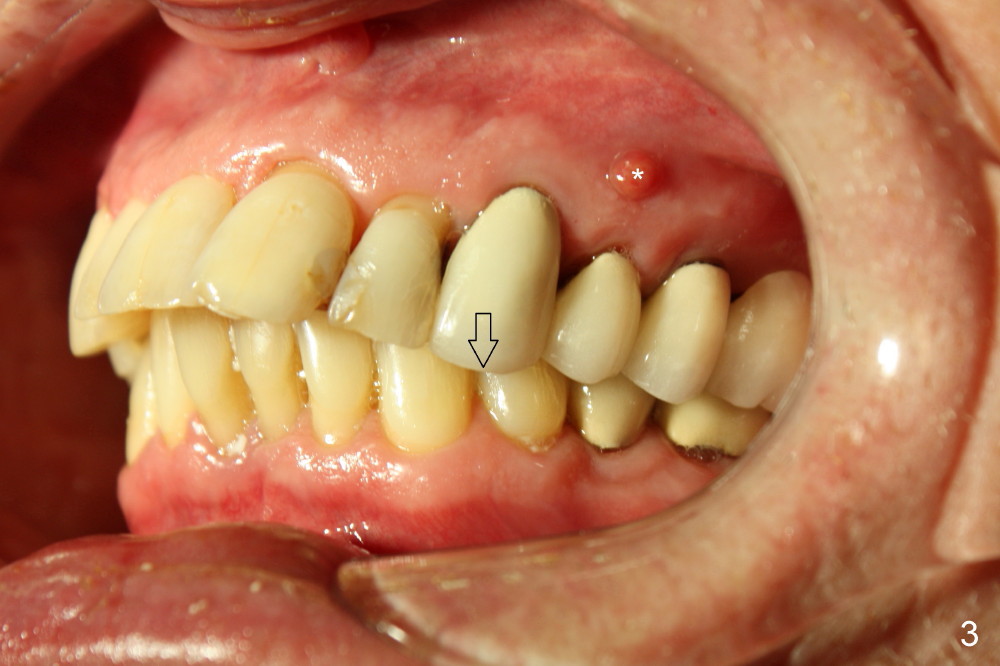

A 66-year-old man has dreamed to correct his bite since childhood. The malocclusion is characterized by deviation of the upper midline to the left (Fig.2), Class II occlusion on the right (Fig.1), and Class I occlusion on the left (Fig.3).

Although there is apical infection associated with the upper left first bicuspid (Fig.3 *), orthodontic treatment consists of extraction of a single tooth: the upper right first bicuspid (Fig.4,5: x), minor movement of the posterior teeth (Fig.4,5 smaller arrow) and major movement of the anterior teeth (bigger arrow). Fig.6 shows simulated tooth movement.